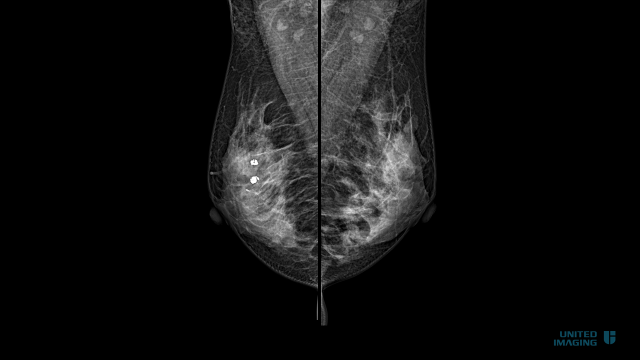

为进一步提高乳腺疾病诊断水平,更好地造福广大百姓,近期我院新引进高清低剂量数字化乳腺DR机。

目前该设备已投入使用。与传统的乳腺钼靶系统相比,影像更清晰直观、定位更准确、照射范围全面,看得更清,查得更放心!确保输出高清的乳腺图像,能有效检出乳腺癌早期的微小病灶,包括针尖状钙化、早期小肿瘤、腋窝淋巴病变等。

乳腺X线检查

让乳腺癌无处可藏

乳腺X线摄影是目前提高早期乳腺癌检出率、降低乳腺癌死亡率的最有效的检查手段之一,特别是有助于发现体检不能触及的乳腺癌,对于彩超和核磁无法鉴别的钙化病变可以进行准确辨别。